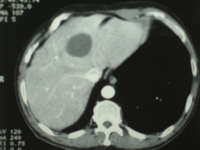

Carcinome hepato cellulaire